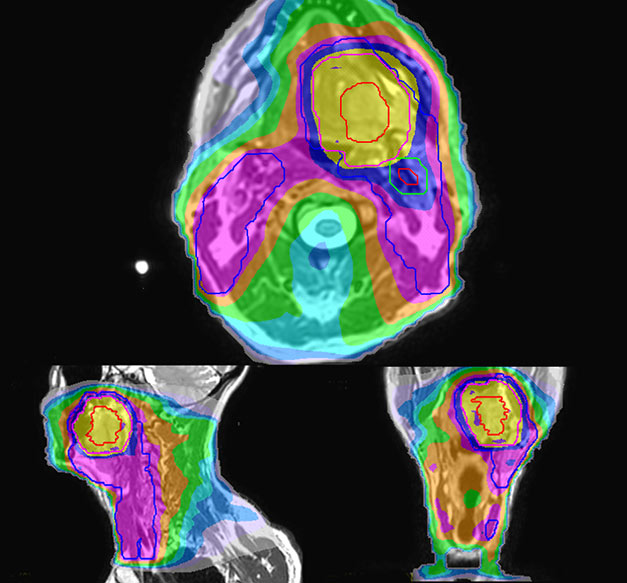

Epidermoid carcinoma of the left tongue base

The patient was diagnosed with an epidermoid carcinoma of the base of the left invading the amygdala lodge and the amygdaloglossal groove. Radiochemotherapy with curative aim was prescribed with a dose of 70 Gy for the tumor, 66 Gy on the suspicious nodes and 56 Gy on the elective drainage areas - in 33 fractions.

MR-based contouring and planning

MR-based target contouring on 3D T2W TSE in transversal, sagittal and coronal planes.

Personalized VMAT dose planned in Philips Pinnacle.